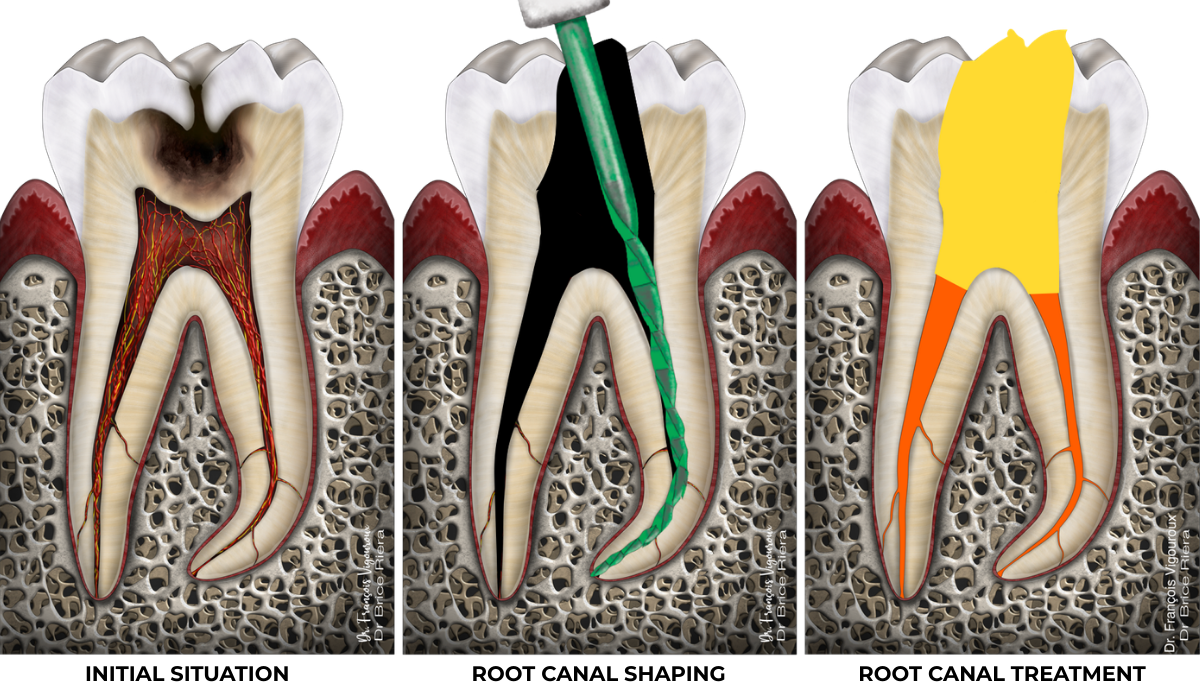

Root canal treatment

There are two situations in which root canal treatment may be indicated.

Either the radicular pulp can no longer be preserved alive (when pulp capping and pulpotomies are no longer possible), generally because the inflammation is too advanced.

Or the pulp is no longer alive and is then described as necrotic.

Anything in the body that is no longer alive becomes infected. Hence the need to disinfect the inside of the tooth (the endodontium): this is root canal treatment.

If the endodontium is infected, this pulpal necrosis may have caused an inflammatory reaction in the bone, known as an apical lesion:

In the absence of an apical lesion, the purpose of root canal treatment is to preserve healthy periapical bone.

When an apical lesion is present, the purpose of root canal treatment is to promote periapical bone healing.

Clinical case

Root canal treatment: 80–95% success rate